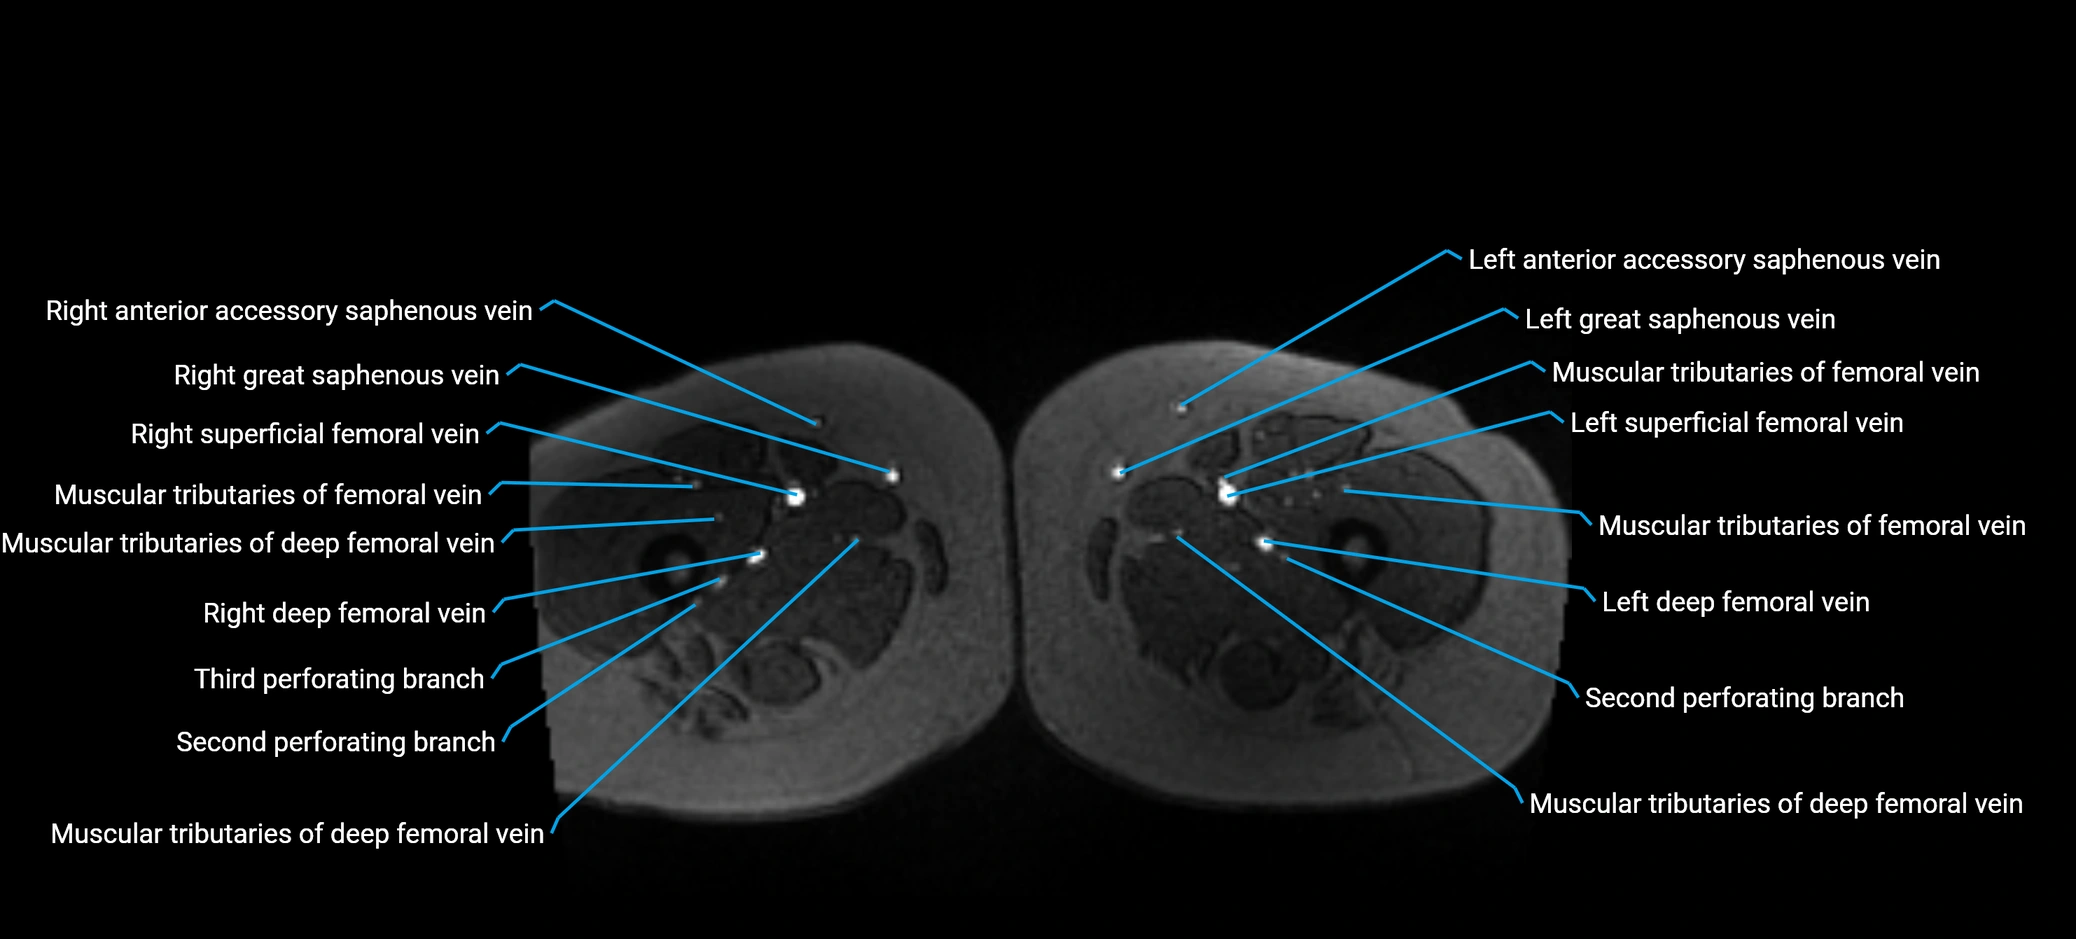

MRI image

image